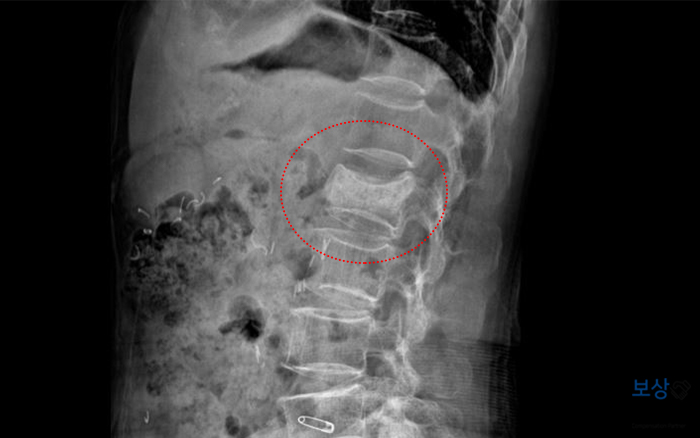

병 명 : S32.090 제2번 요추골절

이 사고로 환자분은 허리 부근의 요추 2번 뼈를 골절 당하시게 되었는데요. 다행히 추가적인 증상은 예상되지 않아서 시술이나 수술 없이 보존적 치료를 시행하게 되었습니다. 그래서 척추 보조기(TLSO) 착용한 상태로 약 3개월간 생활하셔야 했는데요. 몸통을 둘러싸는 매우 불편한 보조기이긴 하지만 안정적인 골유합을 위해서 꼭 착용하셔야 합니다.

회복 후에는 별다른 증상이 안 남을 수도 있는데요. 그런데 척추체의 골절은 찌그러지듯 일어나며, 다시는 원 상태로 돌아오지 않는 것이 특징입니다. 그래서 척추 골절의 경우** 보험약관상 장해 요건에** 해당하기 때문에 반드시 장해 관련 보상을 빠짐없이 받는 것이 중요합니다.